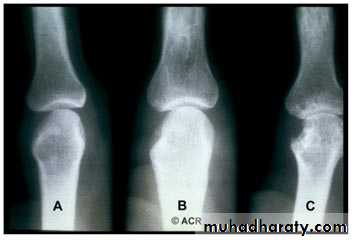

3.Alteration in the shape of the joint.Rheumatoid arthritis :

The changes seen in plain radiograph :Periarticular soft tissue swelling and osteoporosis.

Joint space narrowing .

Bony erosions.

Ulnar deviation.

Shows many features similar to RA but erosions are less prominent . the knee , ankle and wrist are the joints most commonly affected .psoriasis